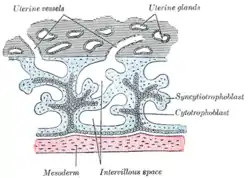

Primary chorionic villi. Diagrammatic. | |

Secondary chorionic villi. Diagrammatic. | |

Syncytiotrophoblast (from the Greek 'syn'- "together"; 'cytio'- "of cells"; 'tropho'- "nutrition"; 'blast'- "bud") is the epithelial covering of the highly vascular embryonic placental villi, which invades the wall of the uterus to establish nutrient circulation between the embryo and the mother. It is a multinucleate, terminally differentiated syncytium, extending to 13 cm.

It is the outer layer of the trophoblasts and actively invades the uterine wall, during implantation, rupturing maternal capillaries and thus establishing an interface between maternal blood and embryonic extracellular fluid, facilitating passive exchange of material between the mother and the embryo.